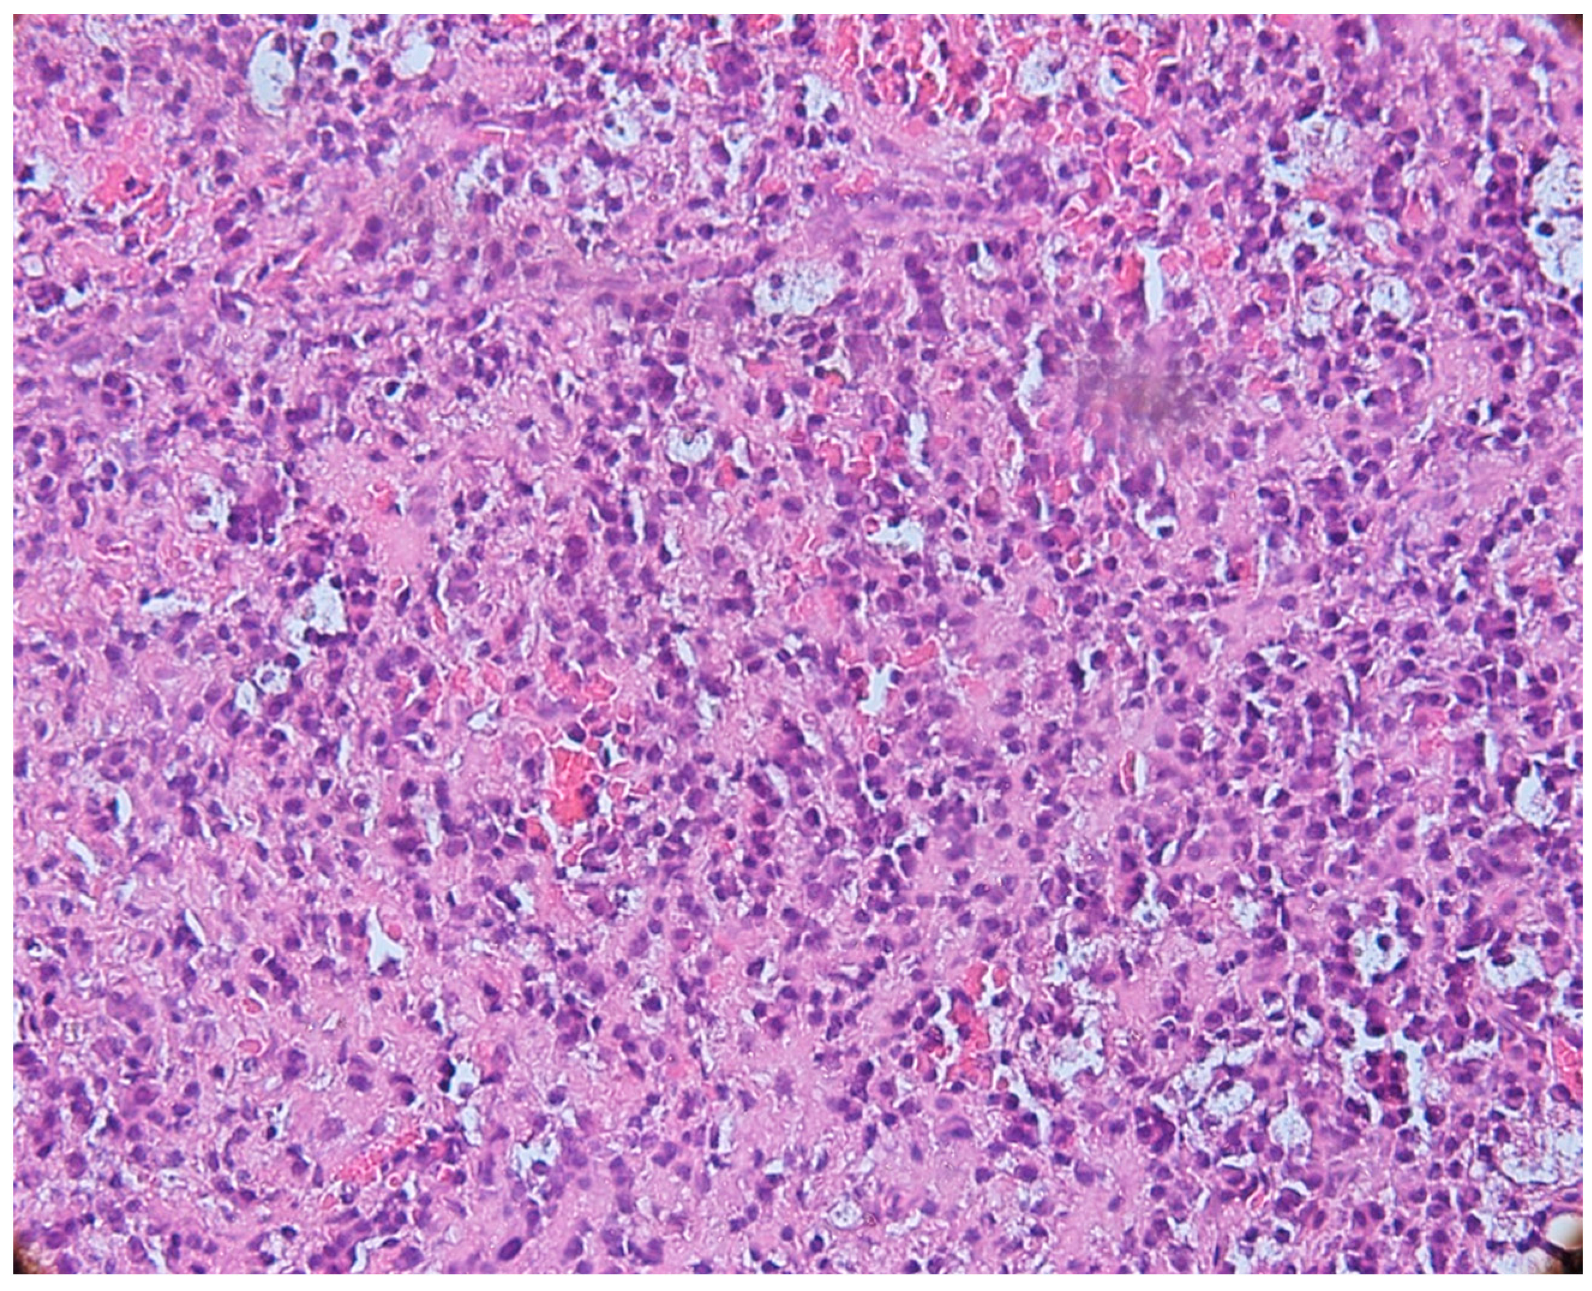

3.2. Mast Cells

3.3. Aspects of Microvessels

3.4. MCD and MVD